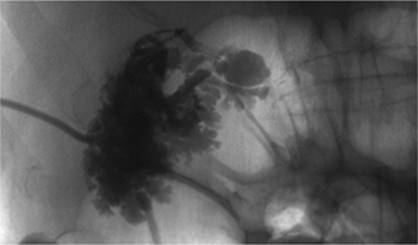

Figure 35.5. A 19-year-old patient with sepsis and cough. A: Axial CT at the level of the midchest demonstrates an 8.5-cm fluid collection in the right posterior hemithorax (asterisk) with compression atelectasis of the adjacent lung. Direct percutaneous access is blocked due to inferior margin of the scapula, overlying ribs, and aerated lung. B: Patient was placed in a left-side-down decubitus position. Change in position provides direct posterior access to the fluid collection. A localizer grid has been placed to mark site of access. C: Access gained with micropuncture needle system and then a 14 Fr drain placed over a wire. Fluid aspirated with syringe and then drain was secured in place and connected to suction bulb. D: Postdrain placement CT. (Case courtesy of Lauren Alexander, MD, Gainesville, FL.)